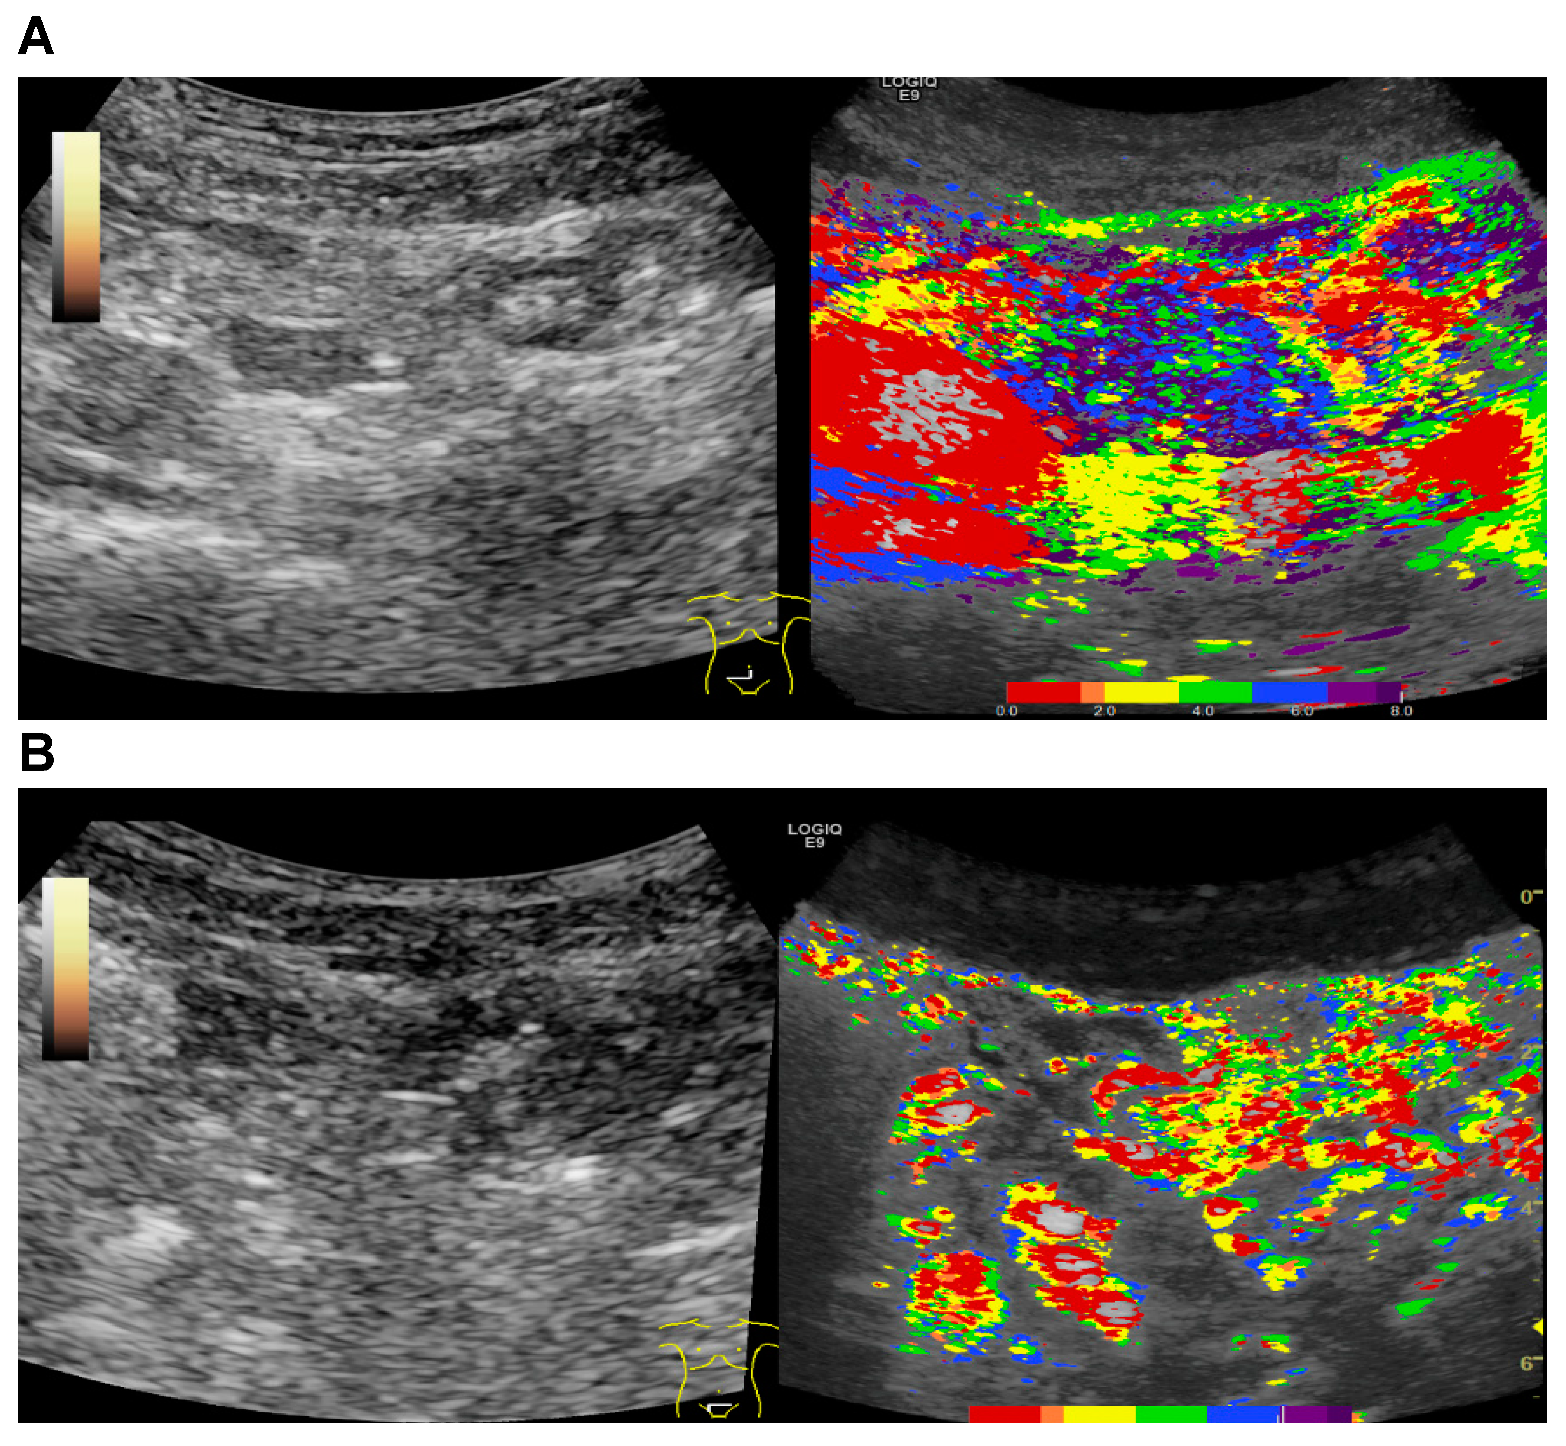

2.4. CEUS

2.5. Parametric Analysis

2.6. Ultrasound Image Analysis